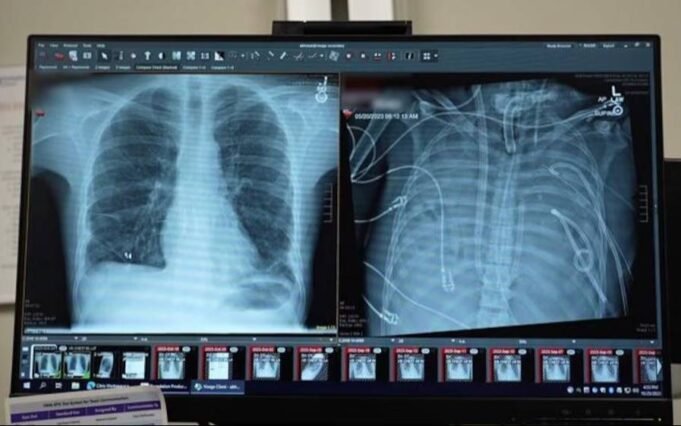

Los pulmones nuevos (izquierda) y los pulmones viejos (derecha) del paciente (Northwestern Medicine)